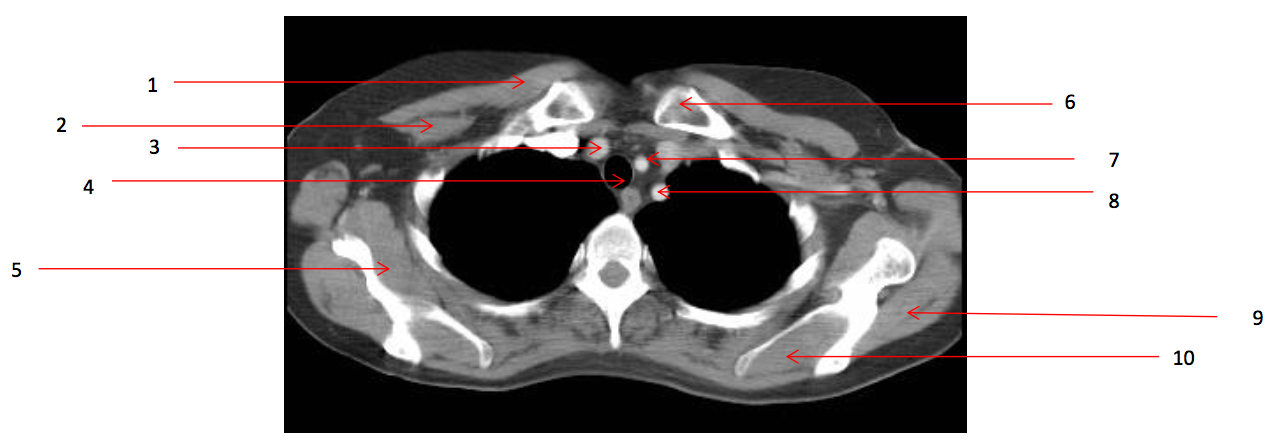

Number 2?

Rt pectoralis minor muscle

Number 6?

Lt clavicle

Number 1?

Rt pectoralis major muscle

Number 8?

Lt subclavian artery

Number 4?

Trachea

Number 7?

Lt common carotid artery

Number 5?

Rt subscapularis muscle

Number 9?

Lt infraspinatus muscle

Number 3?

Brachiocephalic artery